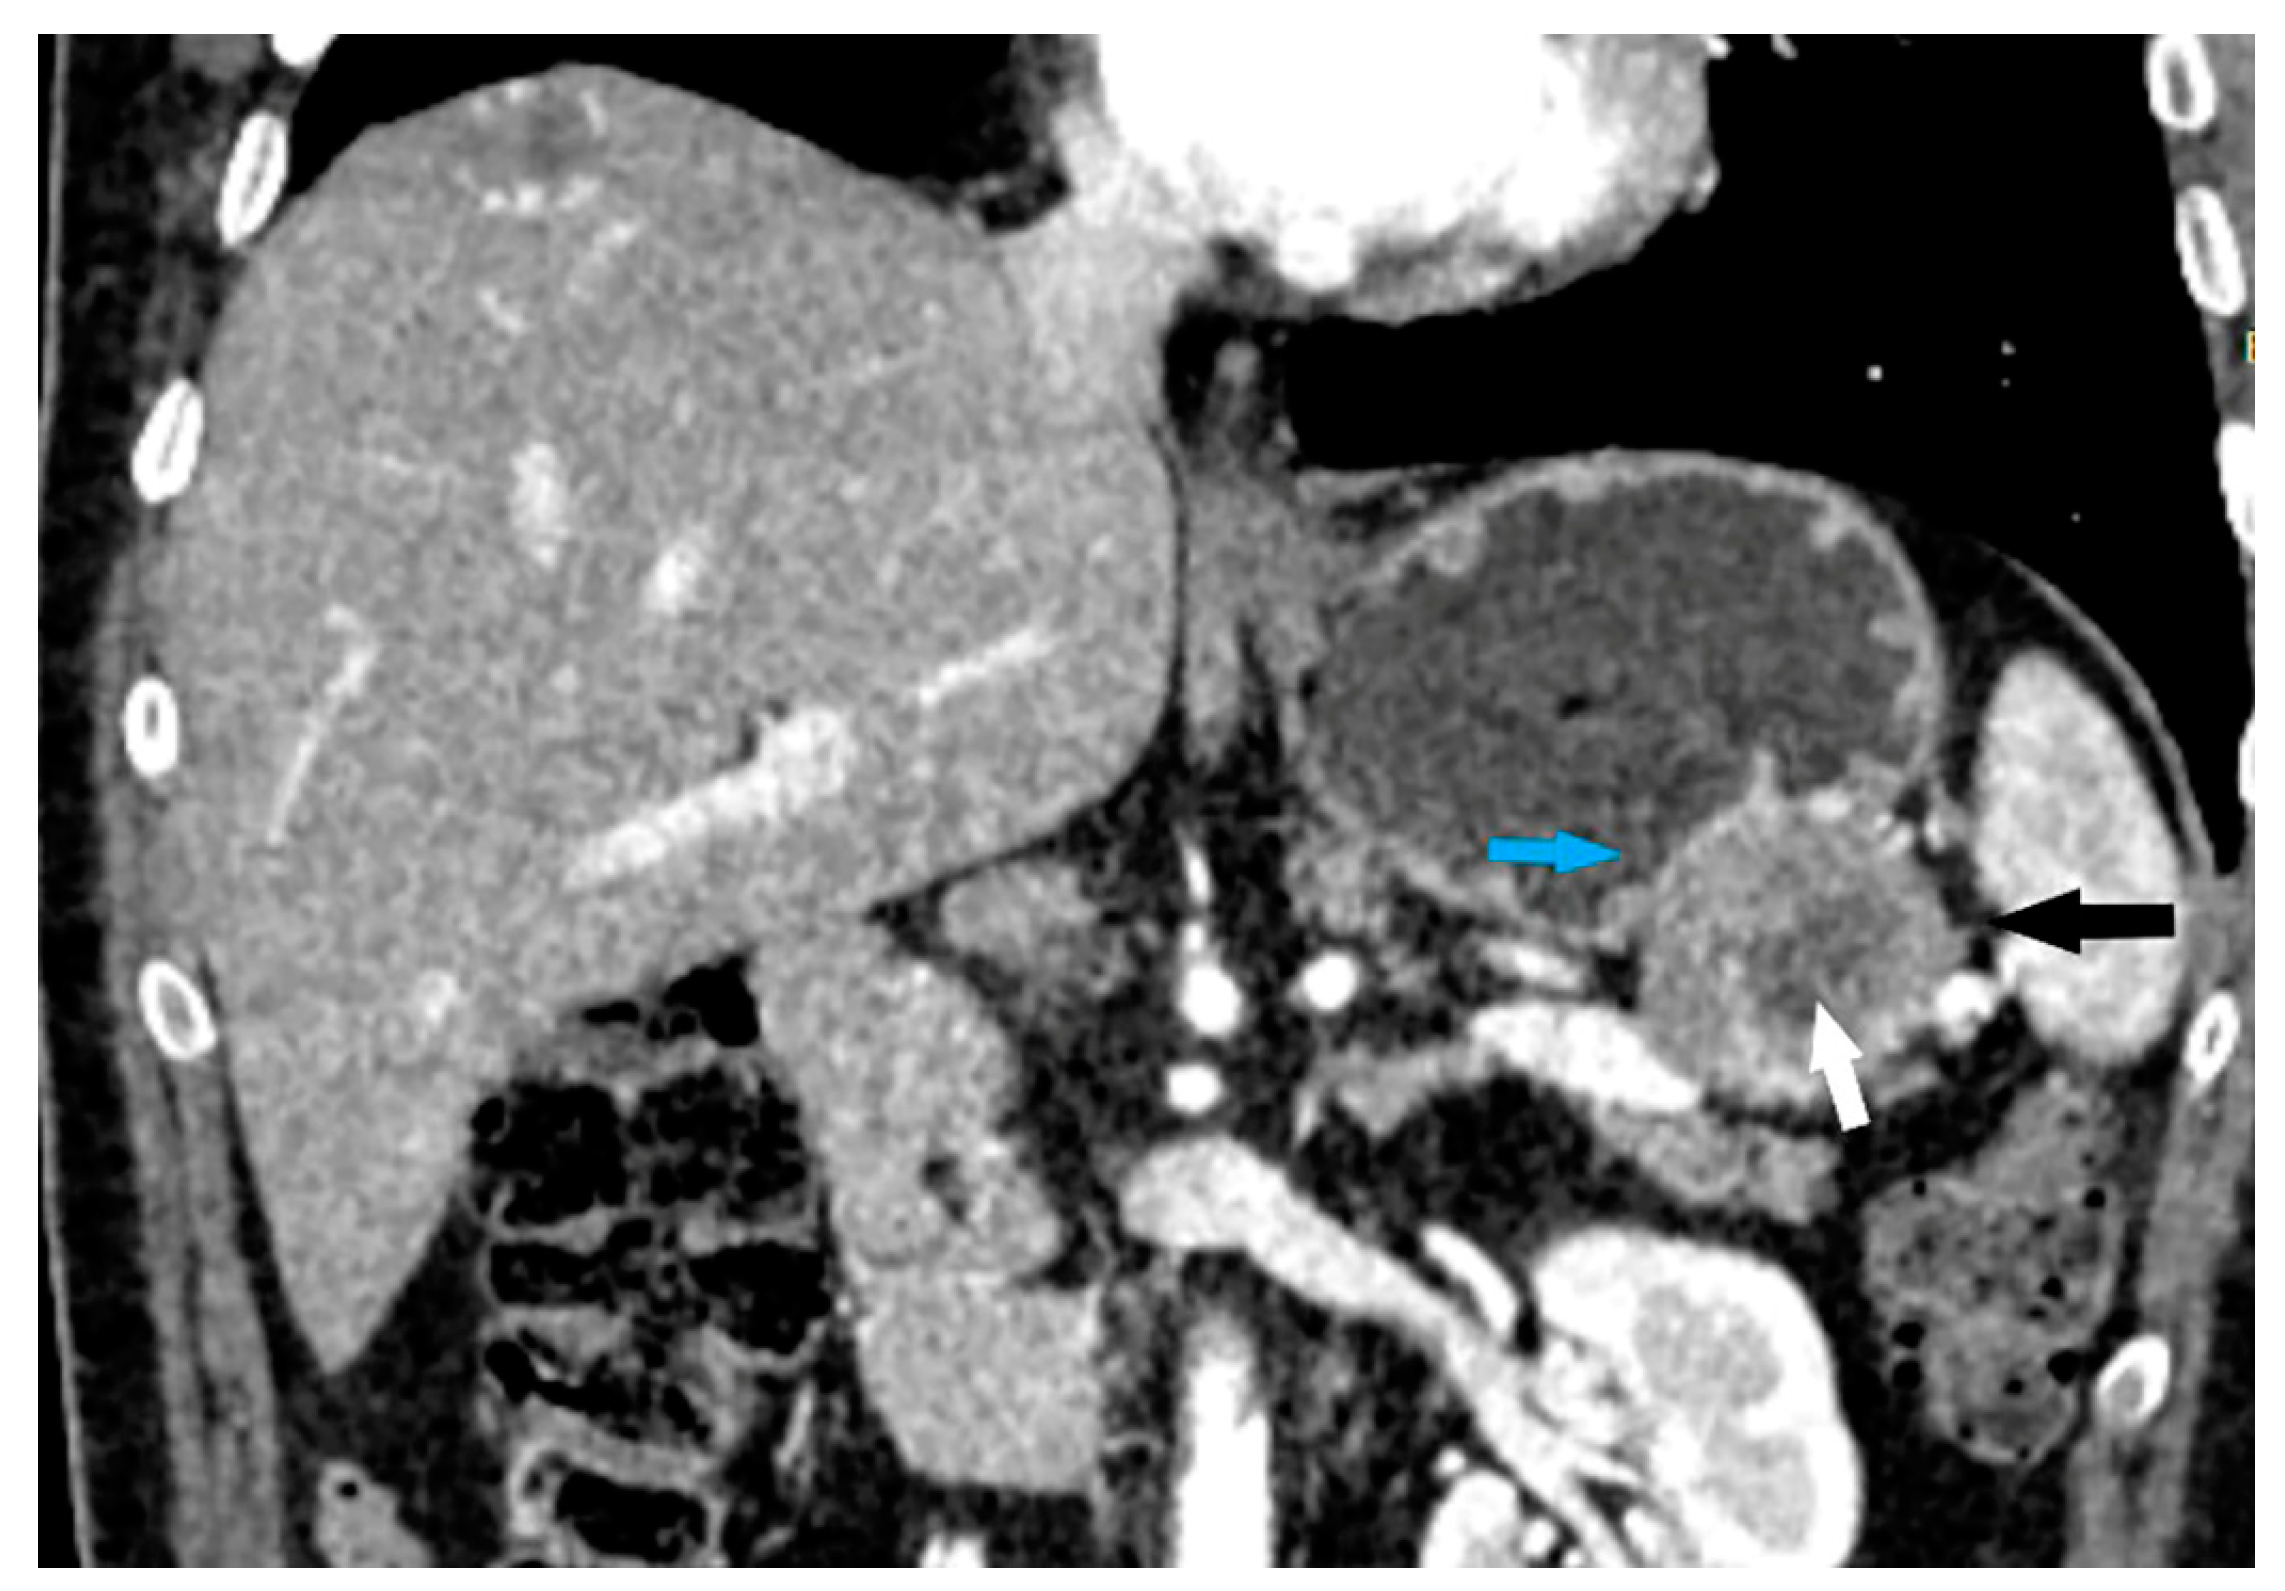

- Maximum diameter: the largest diameter of the tumor in mm (Figure 1);

- Tumor shape: regular or irregular (Figure 1);

- Growth mode: exophytic/mixed and endophytic (Figure 1);

- The presence of visible enlarged vascular structures draining/feeding the tumor (EFDV “enlarged feeding or draining vessel”) (Figure 6);